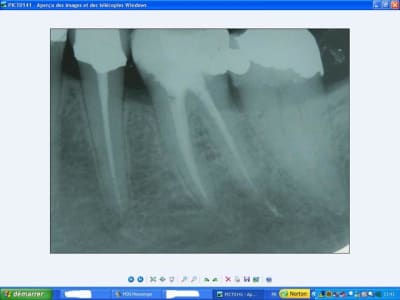

26préop jeoz4o - Eugenol

26postop sqas0w - Eugenol

je ne sais pas quand la 46 a été extraite. C'est vrai qu'à la radio cela semble un peu frais. Le rapport de l'inter ave la gencive semble tout à fait convenable en bouche.

Après, il aurait peut être fallu attendre encore un peu. Mais je ne récupère le cas qu'en cours de route, alors difficile de se faire un jugement.